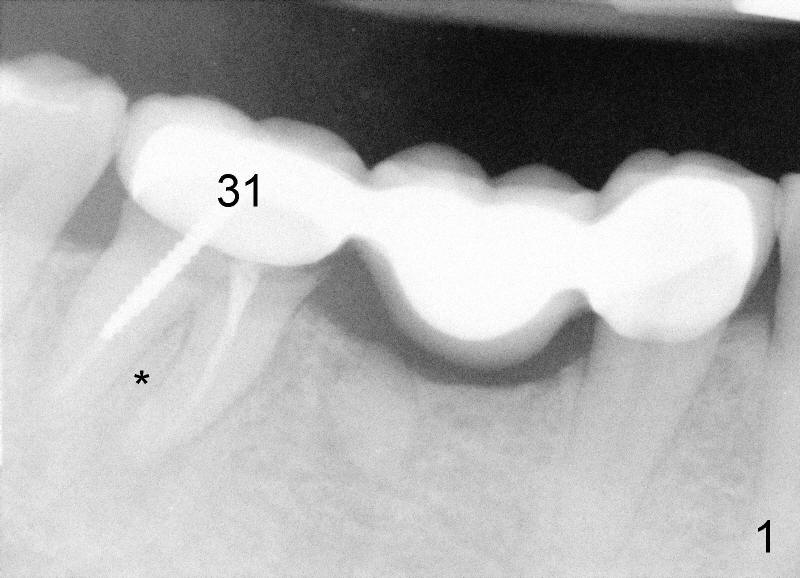

Fifty-three year old man complains that he has difficulty eating in the lower right quadrant. Exam shows that there is 2nd caries underneath #31 retainer and that there is a residual root under #30 pontic (Fig.1). * indicates the septum between the mesial and distal roots of the abutment #31. The teeth #30 and 31 are surgically extracted (Fig.2; *: the septum of #31). A month later, the wound heals (Fig.3).